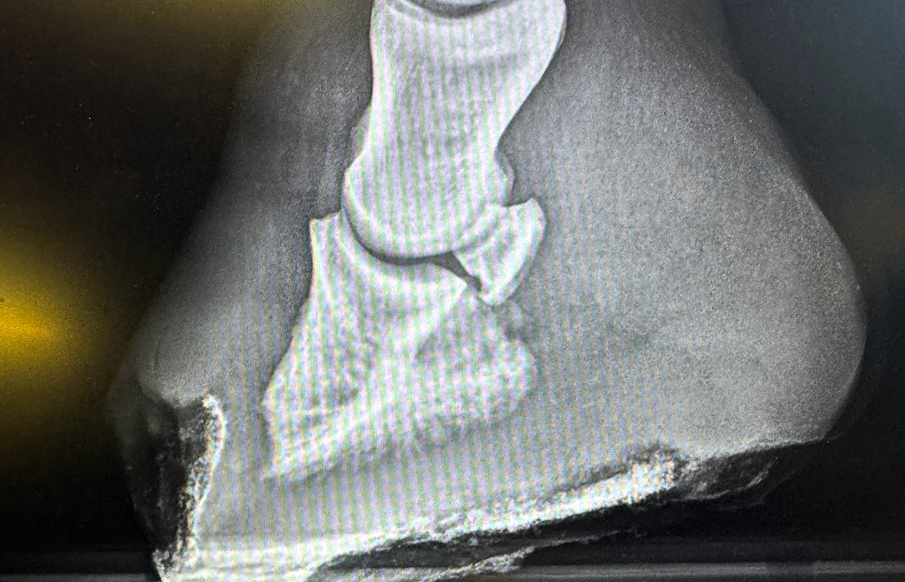

A close-up of a foot with a visibly broken toe, showing swelling and bruising around the injury.

X-rays are commonly used to examine bones and joints for fractures, joint degeneration, arthritis, or bone infections. For example, X-rays can help identify fractures or hoof problems in sheep, horses, cattle, and goats.  Ultrasound can be used to provide insight into ligament injuries that might not be visible on X-rays.